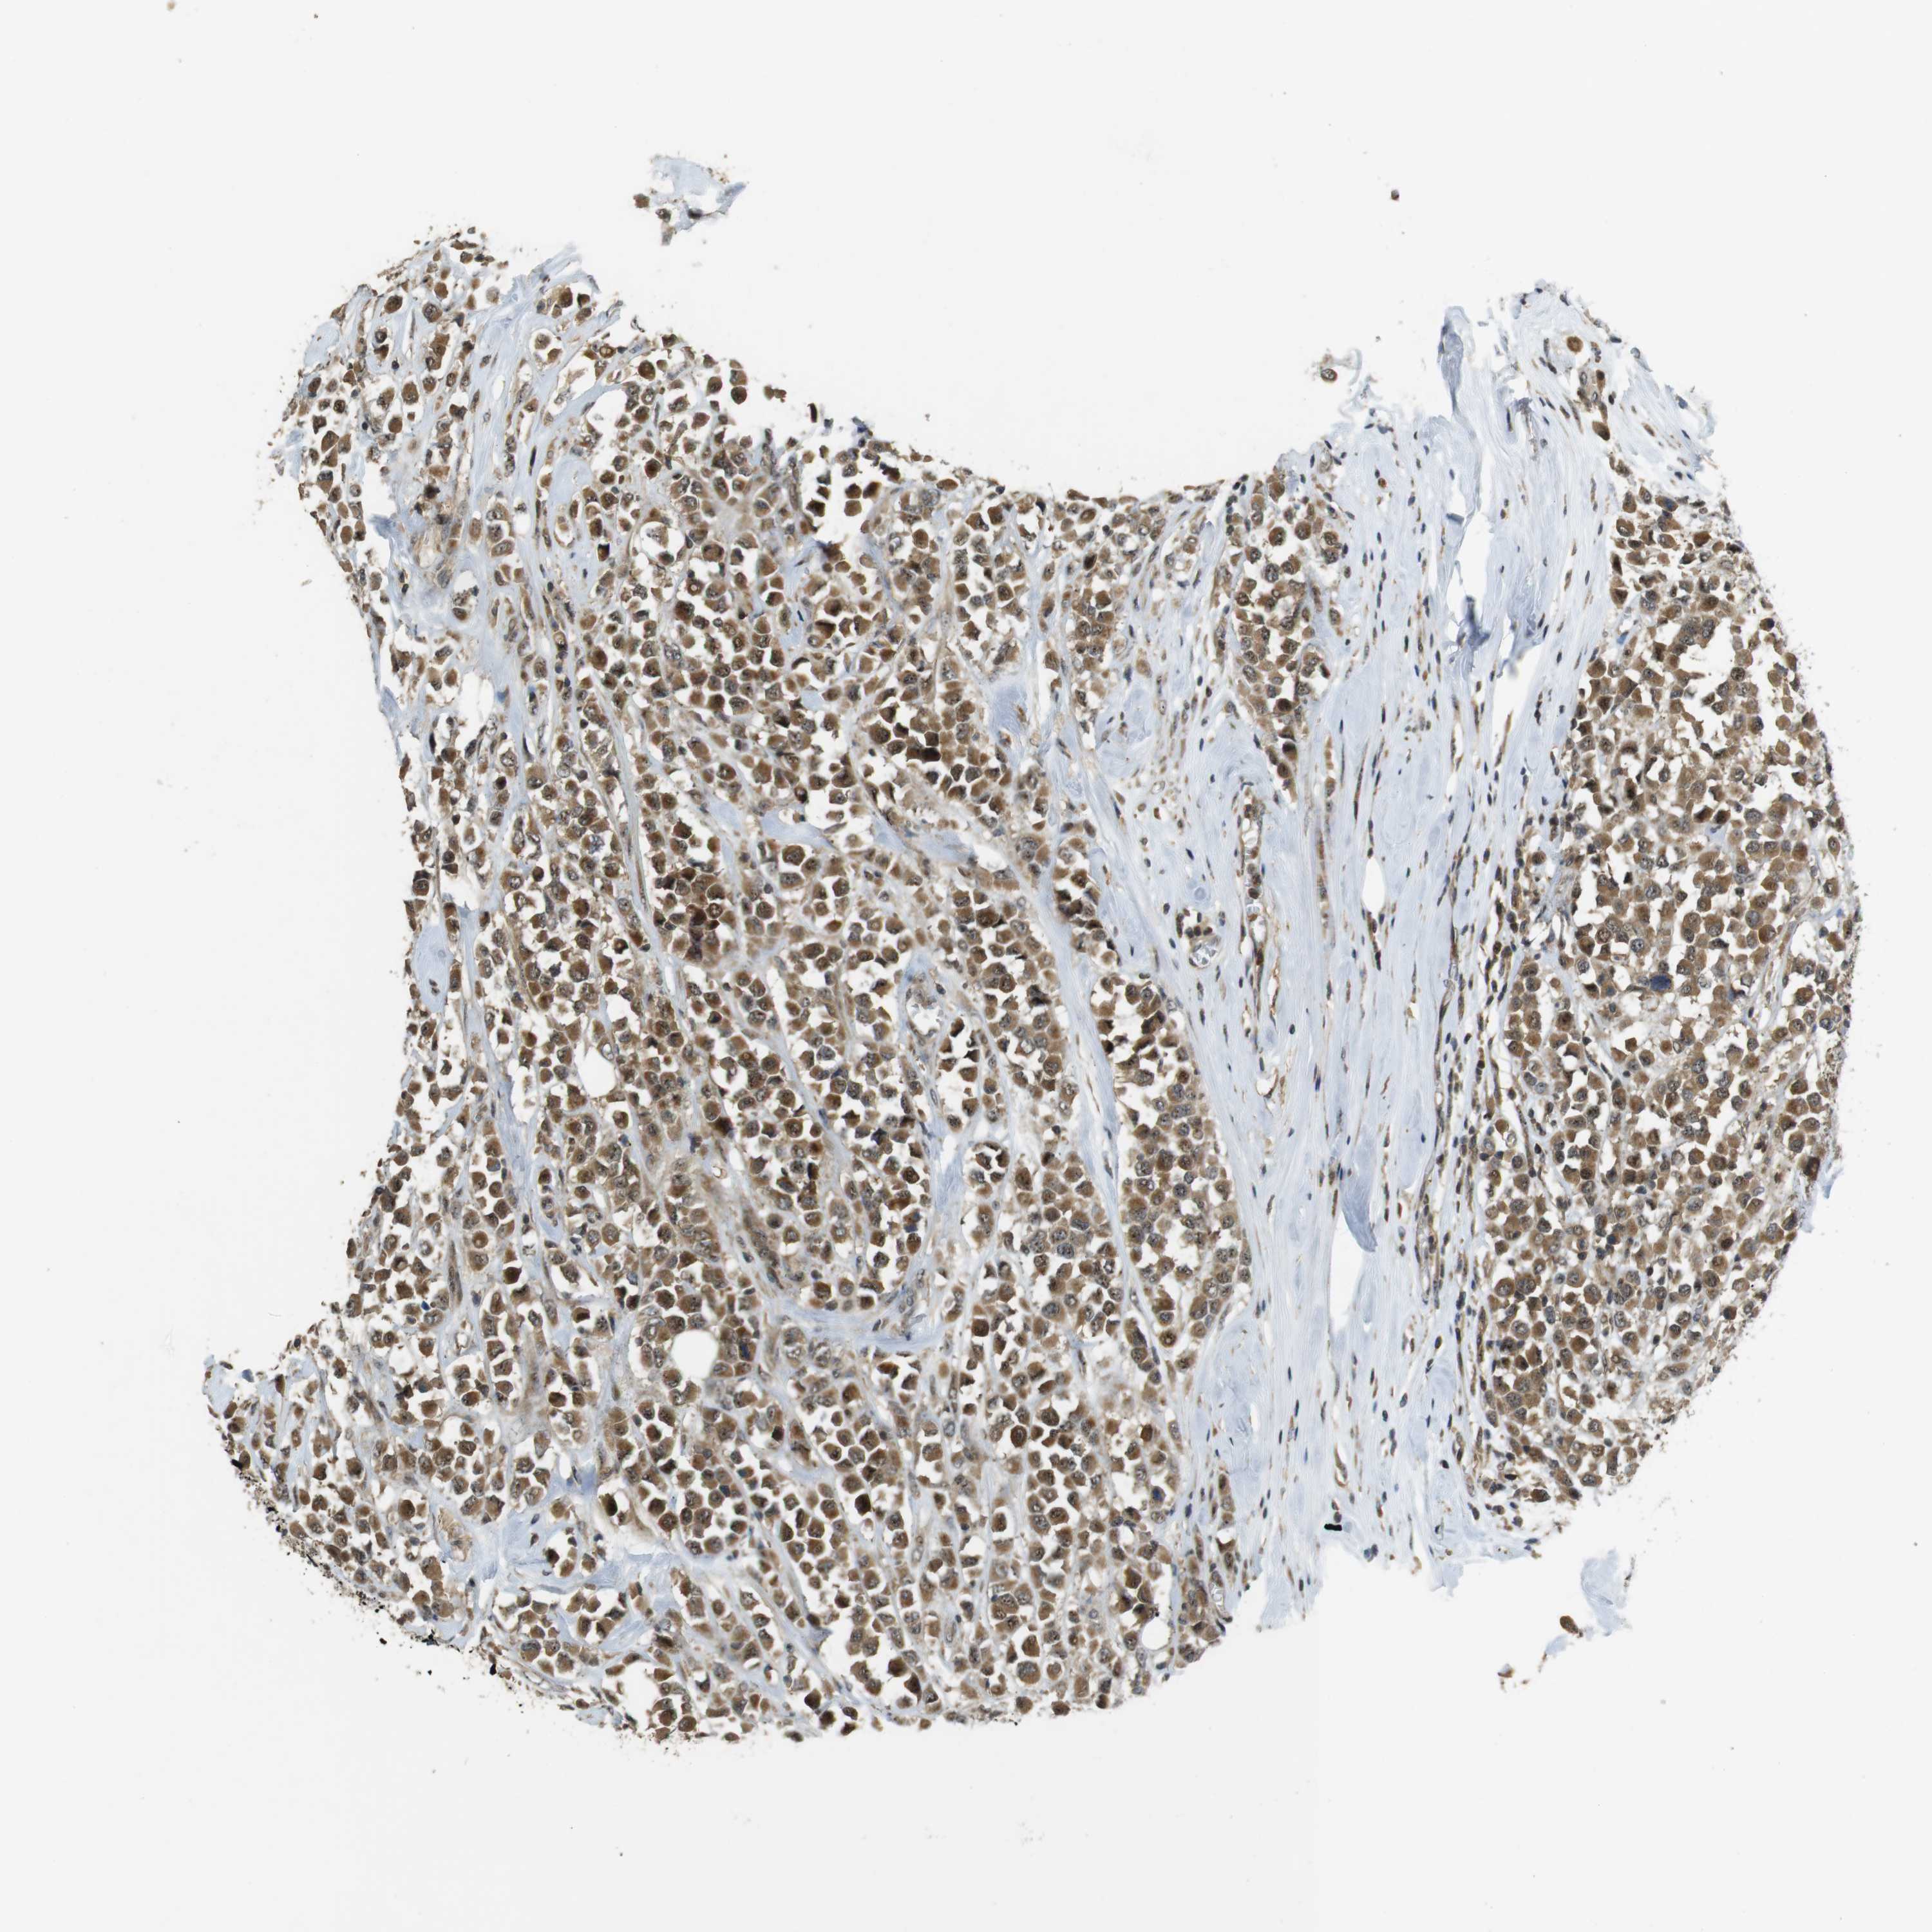

BRCA TCGA BRCA VALIDATION PROTEIN EXPRESSION

ANTIBODIES

AND

VALIDATION